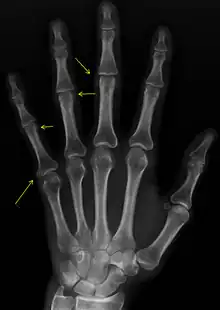

| CREST syndrome (calcinosis and sclerodactyly) | |

CREST causes thickening and tightening of the skin with deposition of calcific nodules ("calcinosis").

Sclerodactyly

Though it is the most easily recognizable manifestation, it is not prominent in all patients. Thickening generally only involves the skin of the fingers distal to the metacarpophalangeal joints in CREST. Early in the course of the disease, the skin may appear edematous and inflamed. Eventually, dermal fibroblasts overproduce extracellular matrix leading to increased tissue collagen deposition in the skin. Collagen cross-linking then causes a progressive skin tightening. Digital ischemic ulcers commonly form on the distal fingers in 30–50% of patients.[3]